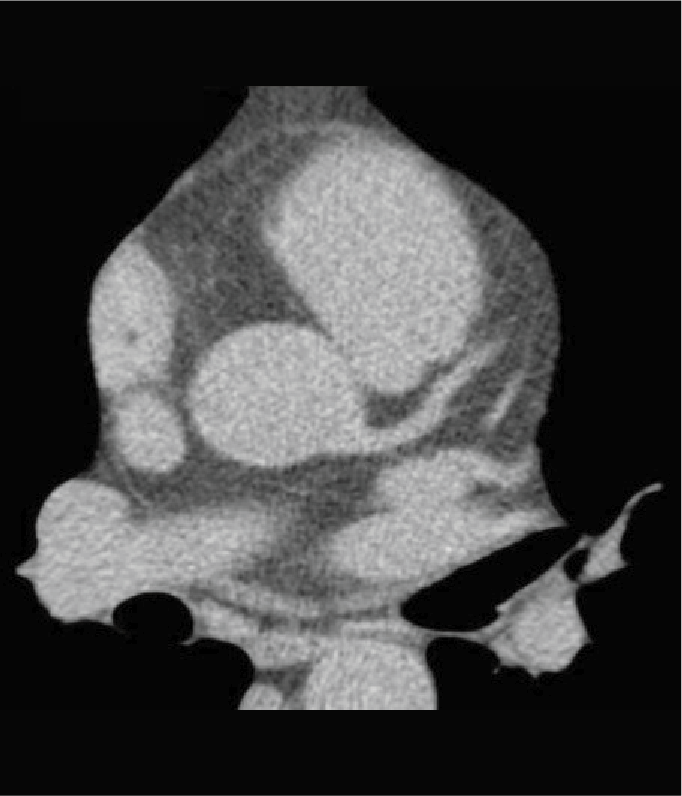

Tomografía cardiaca

Este estudio es adquirido con un tomógrafo de alta velocidad y baja radiación que permite evaluar las arterias coronarias y demostrar la ausencia o la presencia de placas ateromatosas, que son las que ocasionan un infarto (enfermedad arterial coronaria). Mediante la emisión de rayos X es posible obtener imágenes bidimensionales y tridimensionales del exterior y del interior de las arterias coronarias, del corazón y de la función cardiaca.

Cuando es necesario hacer una evaluación mas precisa de tus arterias coronarias la tomografía cardiaca permite, mediante la inyección de contraste por una vena del brazo, estudiar el interior de las arterias y demostrar si existen o no placas que impiden el paso de sangre hacia el corazón, a esta modalidad de la tomografía cardiaca le conocemos como angiotomografía coronaria, que se adquiere en 30 a 60 minutos, y es hoy día el estudio mas confiable para evaluar en forma no invasiva las arterias que nutren al corazón y que cuando se enferman pueden ocasionarte un infarto.

Existen otras indicaciones de la tomografía cardiaca que permiten evaluar las válvulas del corazón y de los grandes vasos como la aorta.